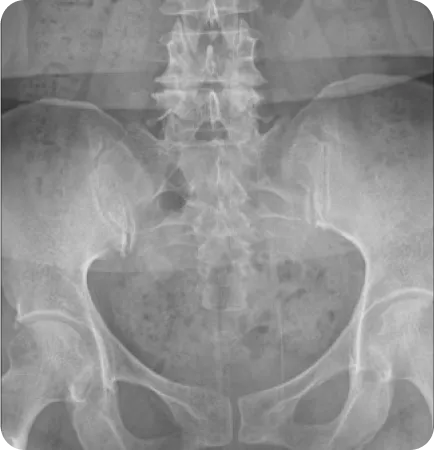

Before & After

해당 사진은 수정없는 실제 치료사진입니다.

환자의 치료결과는 환자의 상태, 치료방법 등에 따라 차이가 발생할 수 있습니다.